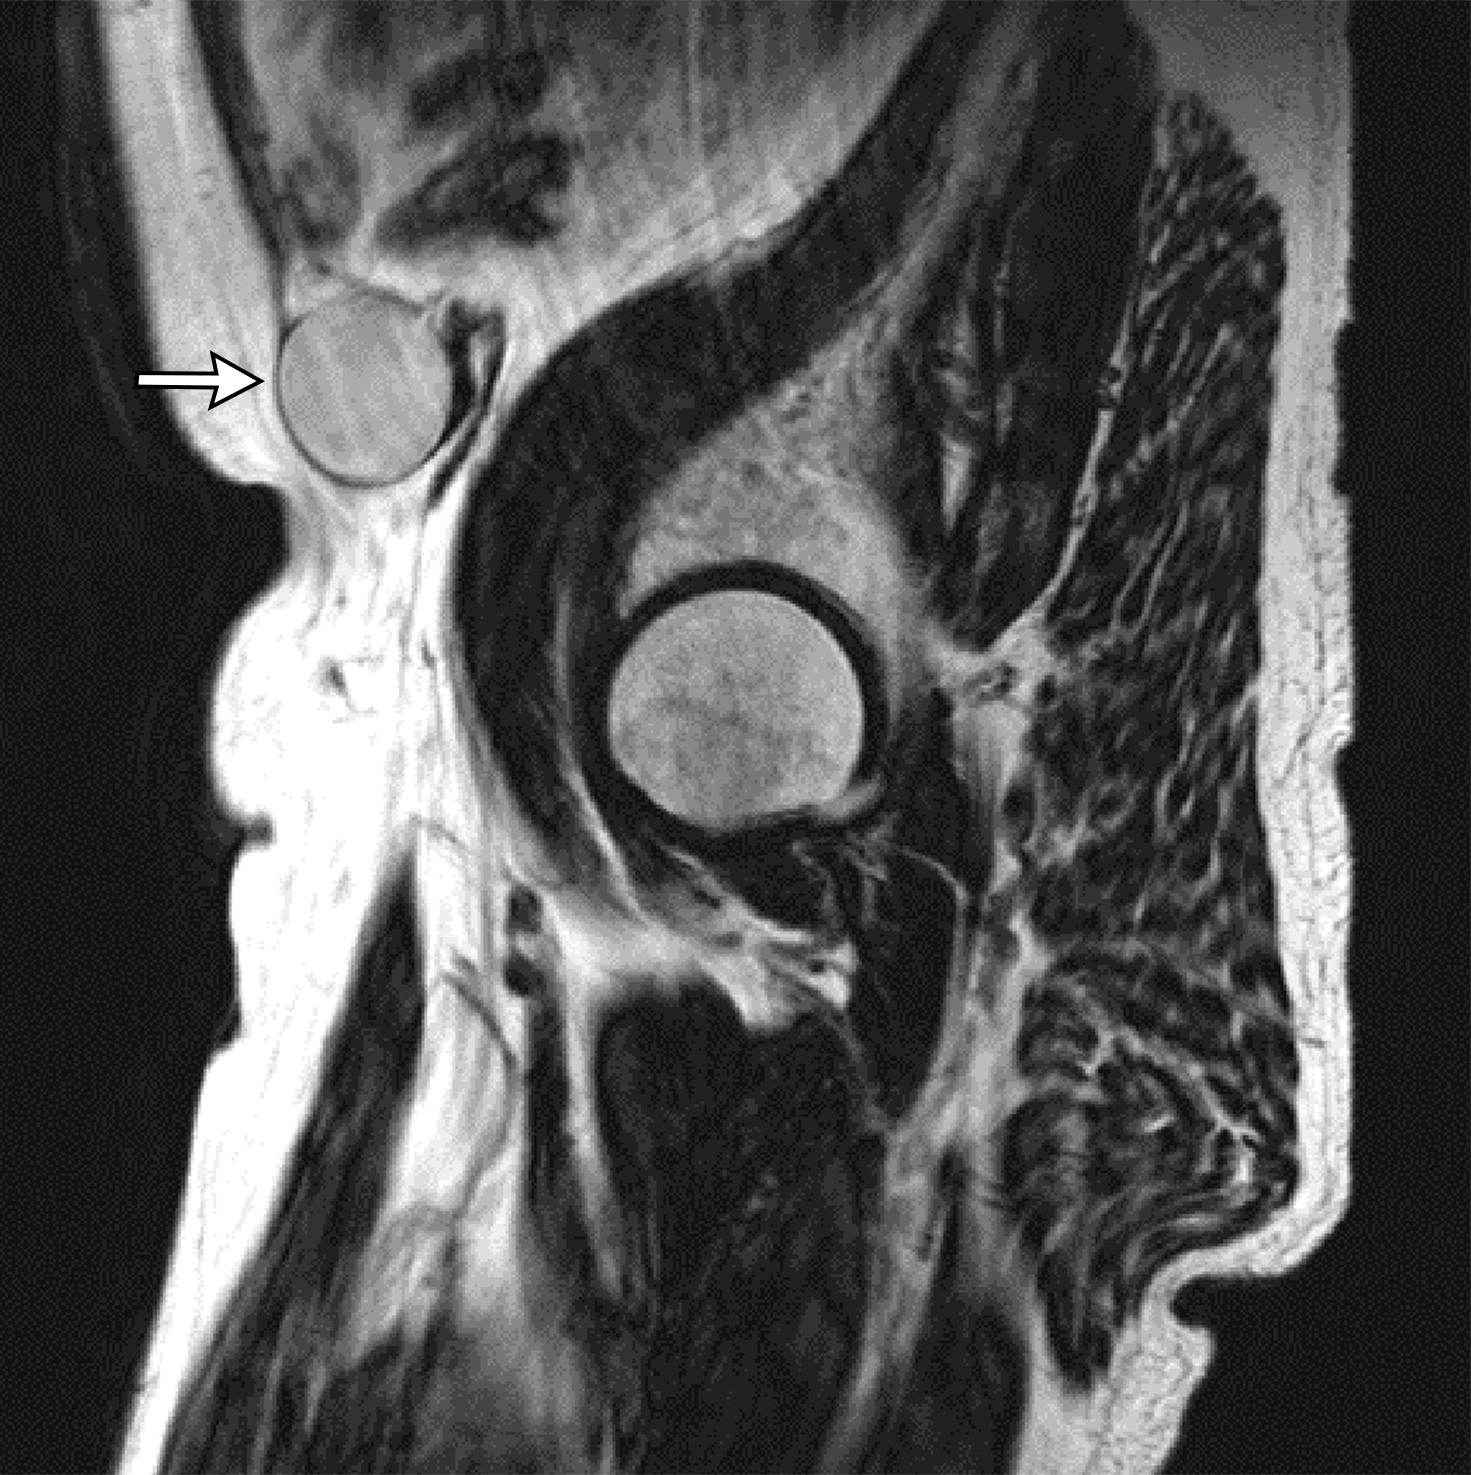

膜性尿道长度(MUL)的测量,注意膜性尿道的近端被前列腺尖端覆盖。